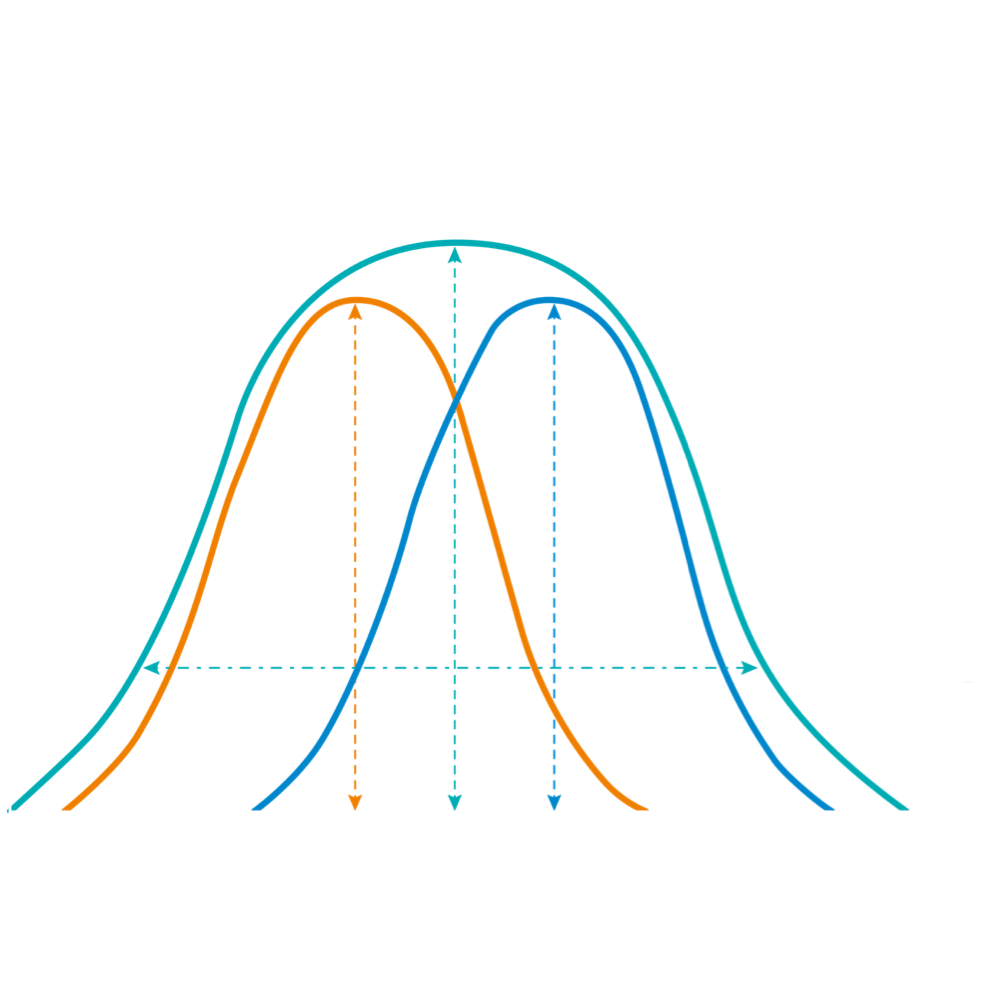

No compromise on resolution nor penetration with ultra-wideband imaging

灵敏度

更高的灵敏度

单晶复合材料

更宽的带宽

传统材料

传统材料

40MHz

50MHz

60MHz

频率(MHz)

单晶超宽频IVUS VS 传统陶瓷材料IVUS

灵敏度

更高的灵敏度

单晶复合材料

更宽的带宽

传统材料

传统材料

40MHz

50MHz

60MHz

频率(MHz)

单晶超宽频IVUS VS 传统陶瓷材料IVUS

米兰官方网站超宽频成像技术覆盖20-80MHz1或20-90MHz2频率范围, 提供优异的分辨力同时也保证充足的穿透深度